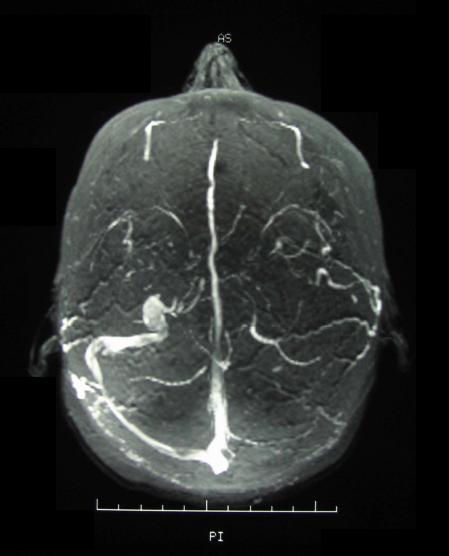

İntrakranyal venöz tromboza beyinde bir toplardamarda ya da toplardamar sinüsünde oluşan kan pıhtısı neden olur. Bu hastanın nöbet geçirmesine neden olabilir. İKVT olan hastalarda koruyucu bir tedavi olarak antiepileptik ilaç verilip verilmemesi gerektiği belirsizdir. Bu grup hastada antiepileptik tedavi kullanmanın potansiyel zararlarına karşı potansiyel faydalarını aydınlatmak istedik.